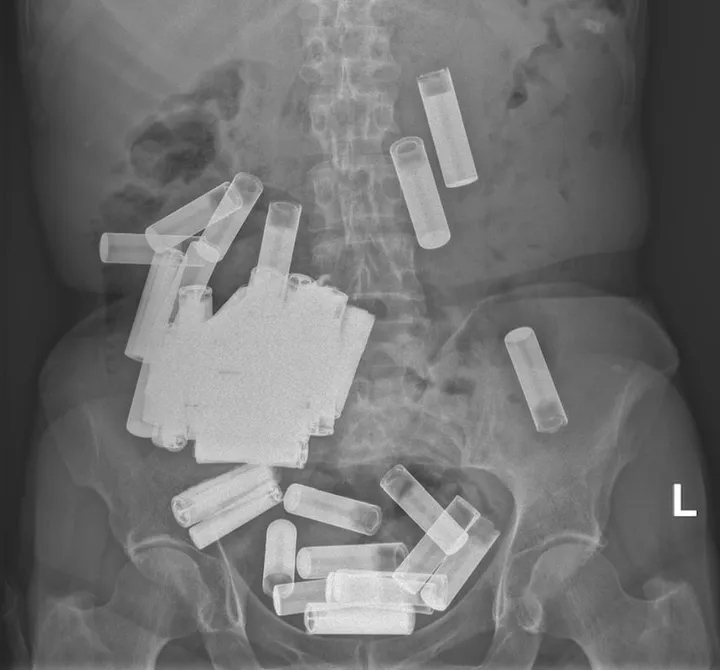

பெண்ணின் வயிற்­றி­லி­ருந்து 55 பற்­ற­றி­களை அகற்­றிய அயர்­லாந்து மருத்­து­வர்கள்

அயர்­லாந்தைச் சேர்ந்த பெண்­ணொ­ரு­வரின் உட­லி­லி­ருந்து 55 பற்­ற­ரி­களை மருத்­து­வர்கள் அகற்­றி­யுள்­ளனர்.

66 வய­தான இப்பெண் வயிற்று வலி­யினால் பாதிக்­கப்­பட்ட நிலையில், அயர்­லாந்தின் தலை­நகர் டப்­ளி­னி­லுள்ள செயின்ற் வின்சென்ட்ஸ் பல்­க­லைக்­க­ழக வைத்­தி­ய­சா­லைக்கு சென்­றி­ருந்தார்.

அப்­பெண்ணை எக்ஸ்றே பரி­சோ­த­னைக்கு உட்­ப­டுத்­தி­ய­போது, அவரின் வயிற்றில் 55 பற்­ற­றிகள் இருப்­பதைக் கண்டு மருத்­து­வர்கள் அதிர்ச்­சி­ய­டைந்­தனர்.

ஒரு­வரின் வயிற்றில் காணப்­பட்ட மிக அதி­க­மன பற்­ற­ரி­களின் எண்­ணிக்கை இது என மருத்­து­வர்கள் தெரி­வித்­துள்­ளனர்

AA  மற்றும் AAA அள­வு­டைய பற்­ற­றிகள் அப்­பெண்ணின் வயிற்றில் காணப்­பட்­டன.

இப்பெண் அடிக்­கடி பற்­ற­றி­களை விழுங்கி வந்­துள்ளார் என்­பது தெரி­ய­வந்­துள்­ளது.

பற்­ற­றி­ரி­களின் பாரம் கார­ண­மாக இப்­பெண்ணின் வயிறு, பூப்­பென்­பு­க­ளுக்கு கீழ் தொங்கிக் கொண்­டி­ருந்­தது என மருத்­து­வர்கள் தெரி­வித்­துள்­ளனர்.

மருந்­துகள் மூலம் மேற்­படி பற்­ற­ரி­களை இயற்­கை­யான முறையில் வெளி­யேற்­று­வ­தற்கு மருத்­து­வர்கள் முயற்­சித்­தனர்.

முதல் வாரத்தில் அப்பெண்  5 பற்­ற­றி­களை வெளி­யேற்­றினார். எனினும் அதன்பின் ஏனைய பற்றிகள் உடலில் சிக்கிக் கொண்டன. அதையடுத்து சத்திரசிகிச்சை மூலம் ஏனைய பற்றறிகள் அகற்றப்பட்டன.